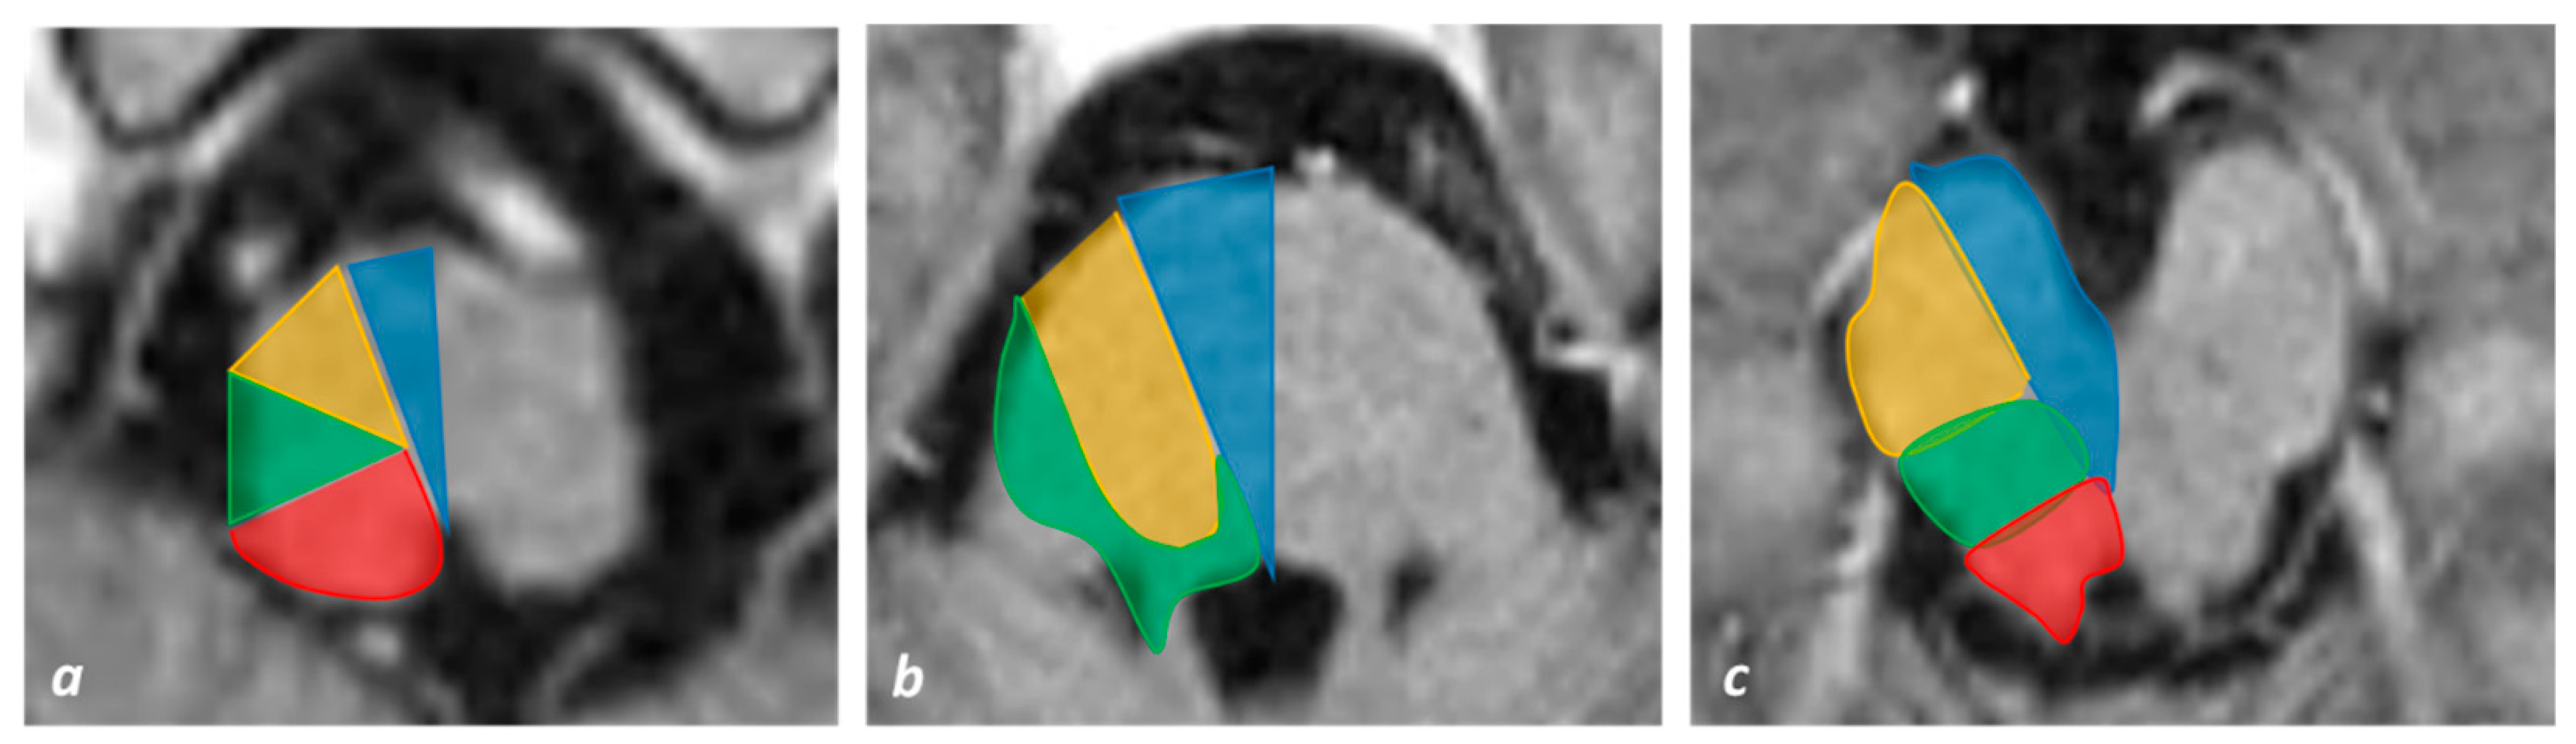

3.1. Medullary Infarction

3.2. Pontine Infarction

3.3. Midbrain Infarction